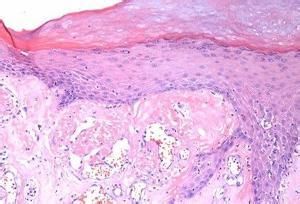

根據臨床表現,結合病理、免疫組化等檢查,能夠確診。注意與溝紋舌、梅-羅綜合徵等進行鑑別。